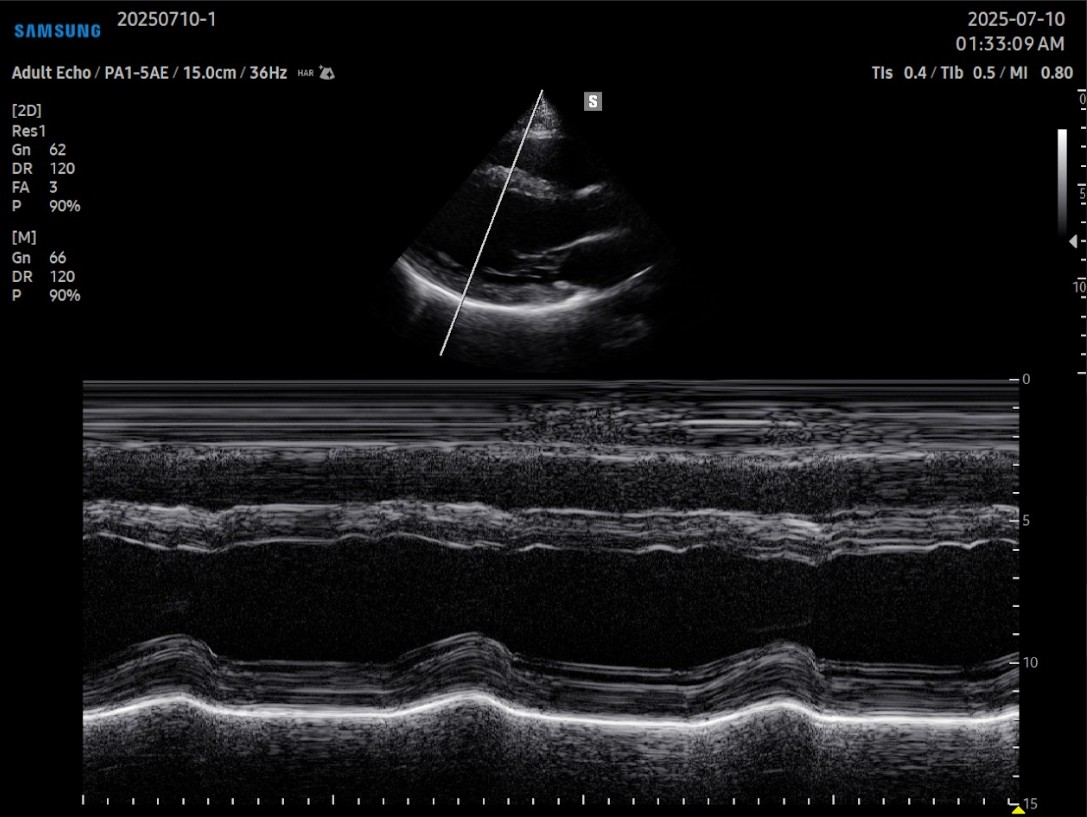

El ecógrafo Samsung V5 es un equipo de última generación que combina tecnologías de imagen avanzadas con herramientas inteligentes basadas en inteligencia artificial, diseñadas específicamente para entornos cardiovasculares.

Con un diseño compacto y movilidad optimizada, el CV5 ofrece una experiencia de usuario fluida, imágenes de alta fidelidad y automatización clínica que mejora la eficiencia y la precisión en el diagnóstico cardiológico.

Entre sus prestaciones más destacadas se encuentran tecnologías como Crystal Architecture™, que proporciona una calidad de imagen clara y detallada incluso en estructuras vasculares profundas, y funciones como HeartAssist™, que permite identificar automáticamente vistas cardíacas estándar, optimizando el tiempo de exploración y reduciendo la variabilidad entre operadores.

El sistema incluye herramientas avanzadas como Strain+™ para el análisis del movimiento de la pared ventricular izquierda, AutoEF™ para cálculo automático de la fracción de eyección, y MV-Flow™ y LumiFlow™, que mejoran la visualización del flujo sanguíneo y la microvasculatura en tiempo real.